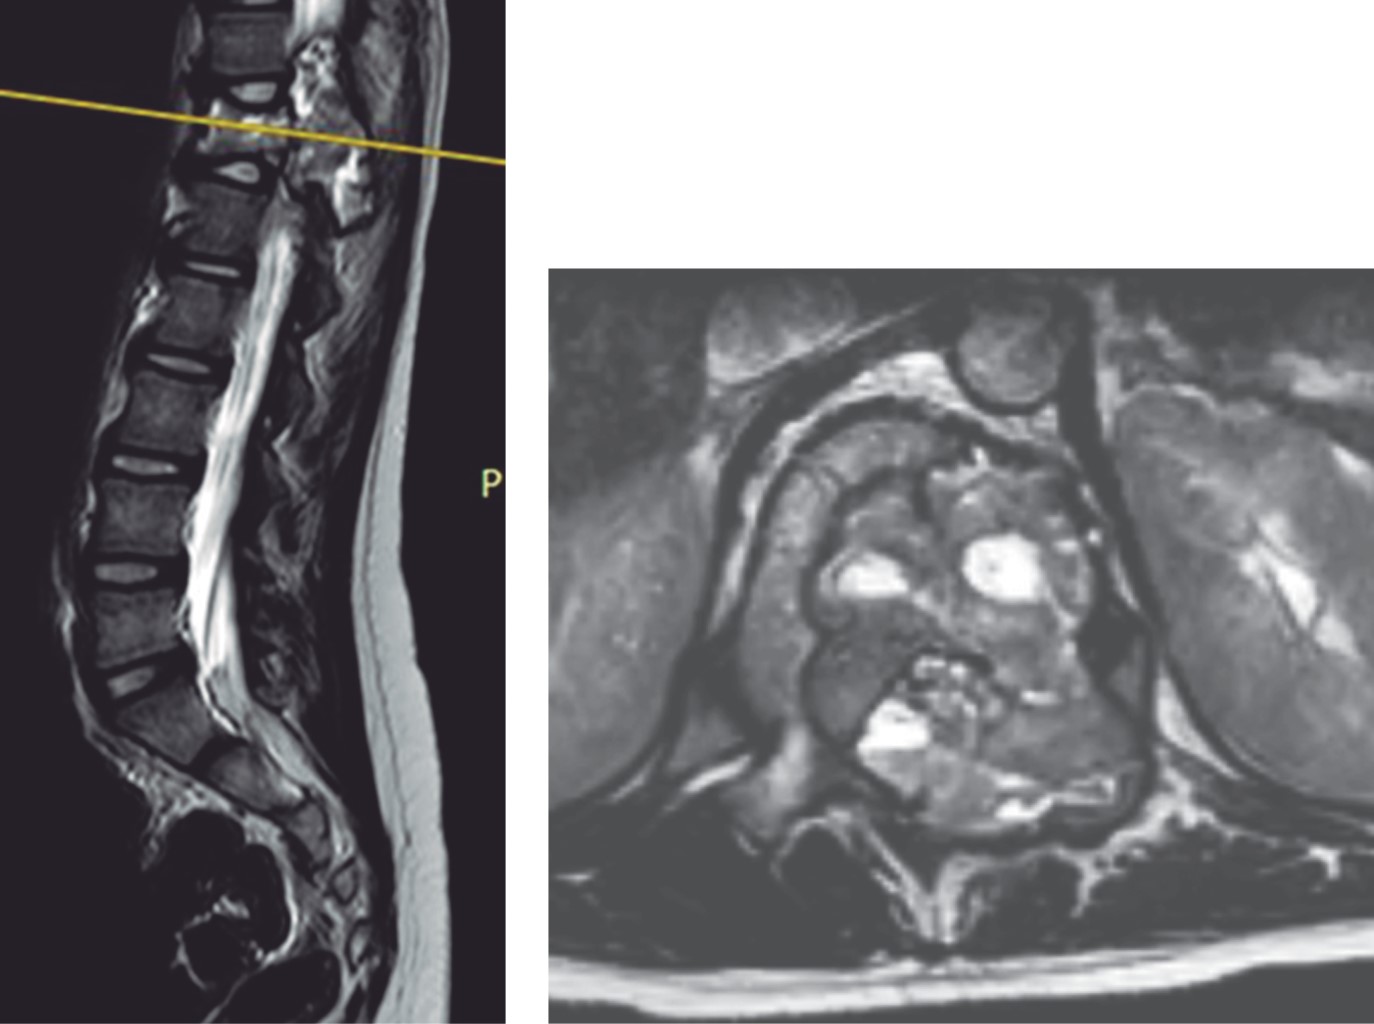

La tomografía toracolumbar mostró una lesión a nivel del cuerpo vertebral T12 y elementos posteriores de lado izquierdo de aspecto expansivo, lítico, con un interior trabeculado (Figura 1).

La RM simple y contrastada caracterizó de mejor forma lesión, siendo extradural, heterogénea, con una porción multilocular con niveles líquido-líquido observados hiperintensos en T2; presentaba también una porción sólida que realzaba al contraste, la cual invadía al canal medular generando invasión anteriormente hacia el cuerpo vertebral, con destrucción del pedículo, proceso transverso y la lámina (Figuras 2, 3, 4, 5 y 6).